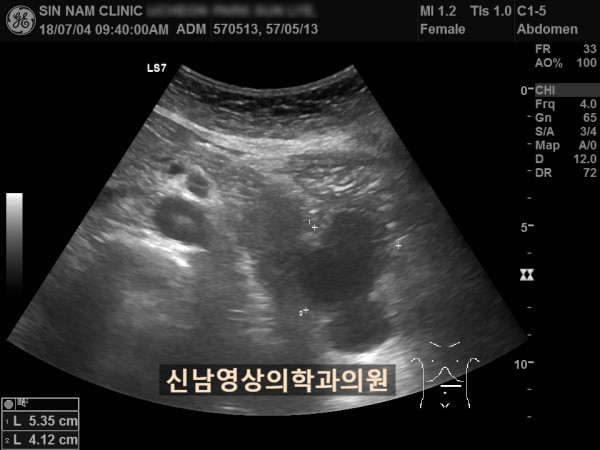

아래 환자분은 60대 여성분으로 식사만 하면 복통이 나타나서 내과에서 위 / 대장 내시경을 받으셨지만 정상으로 진단받았던 분으로 내과에서 복부 초음파검사를 했지만 이상 소견을 발견하지 못했던 분입니다.

초음파 검사는 영상의학과에서 받아야 한다는 주변 지인들의 말씀을 듣고, 본원을 내원해주셨어요.

복부 초음파 검사상 췌장꼬리(미부)에서 발생한 암으로 대장 장간막으로 전이가 되어서 대장내시경에서는 정상으로 확인되었고, 식사를 하면 장간막 전이때문에 장폐색 증상으로 복통이 발생하셨던 것으로 복막으로 전이가 진행되어 복수까지 있었습니다.